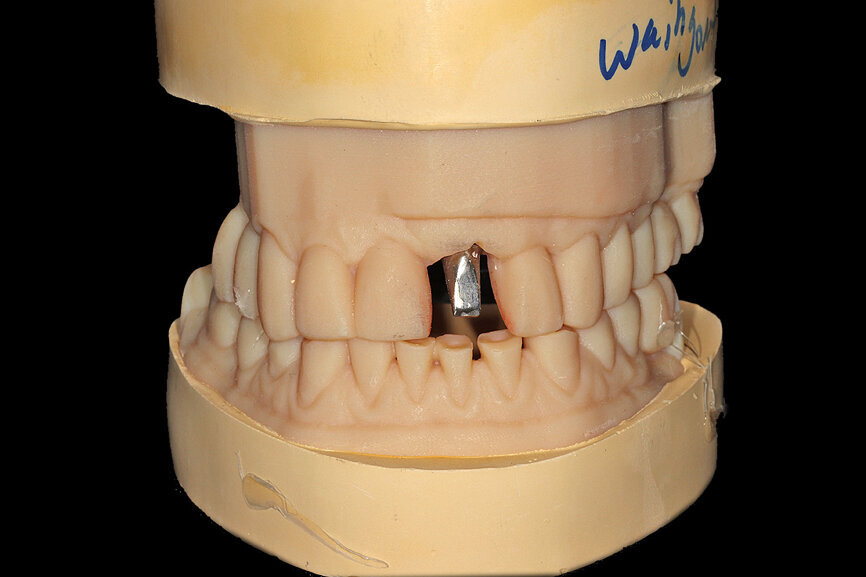

Fig. 16a: The accuracy of the implant and template design allows for true restoratively driven planning combined with CAD/CAM applications for the design

and fabrication of a patient-specific abutment and transitional restoration.

Fig. 16b: The accuracy of the implant and template design allows for true restoratively driven planning combined with CAD/CAM applications for the design

Fig. 26a: The prefabricated CAD/CAM abutment and transitional crown

Fig. 26b: A post-op periapical radiograph confirmed successful sub-crestal placement of

this platform-switched design.

Fig. 26c: The abutment in place.